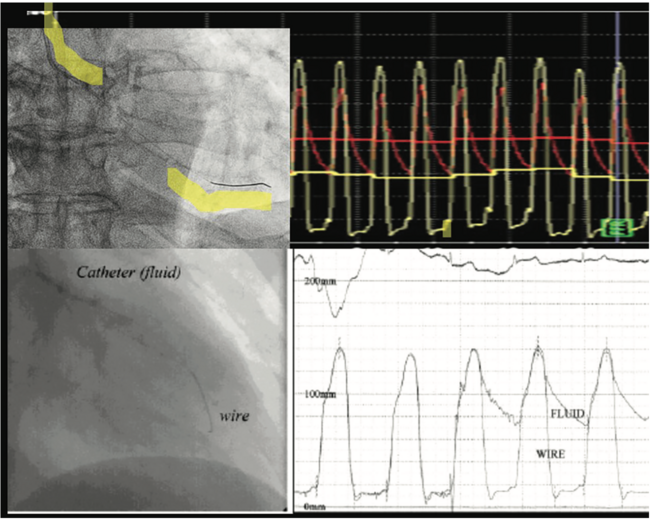

The optimal hemodynamic assessment of an aortic valve gradient is performed with simultaneously acquired aortic and left ventricular pressures. Ideally, we would like to make these measurements in the safest and most accurate way, and for years, cath labs around the world used a femoral artery sheath with a pigtail catheter (1 French [Fr] size smaller) passed through the sheath to the left ventricle (LV).